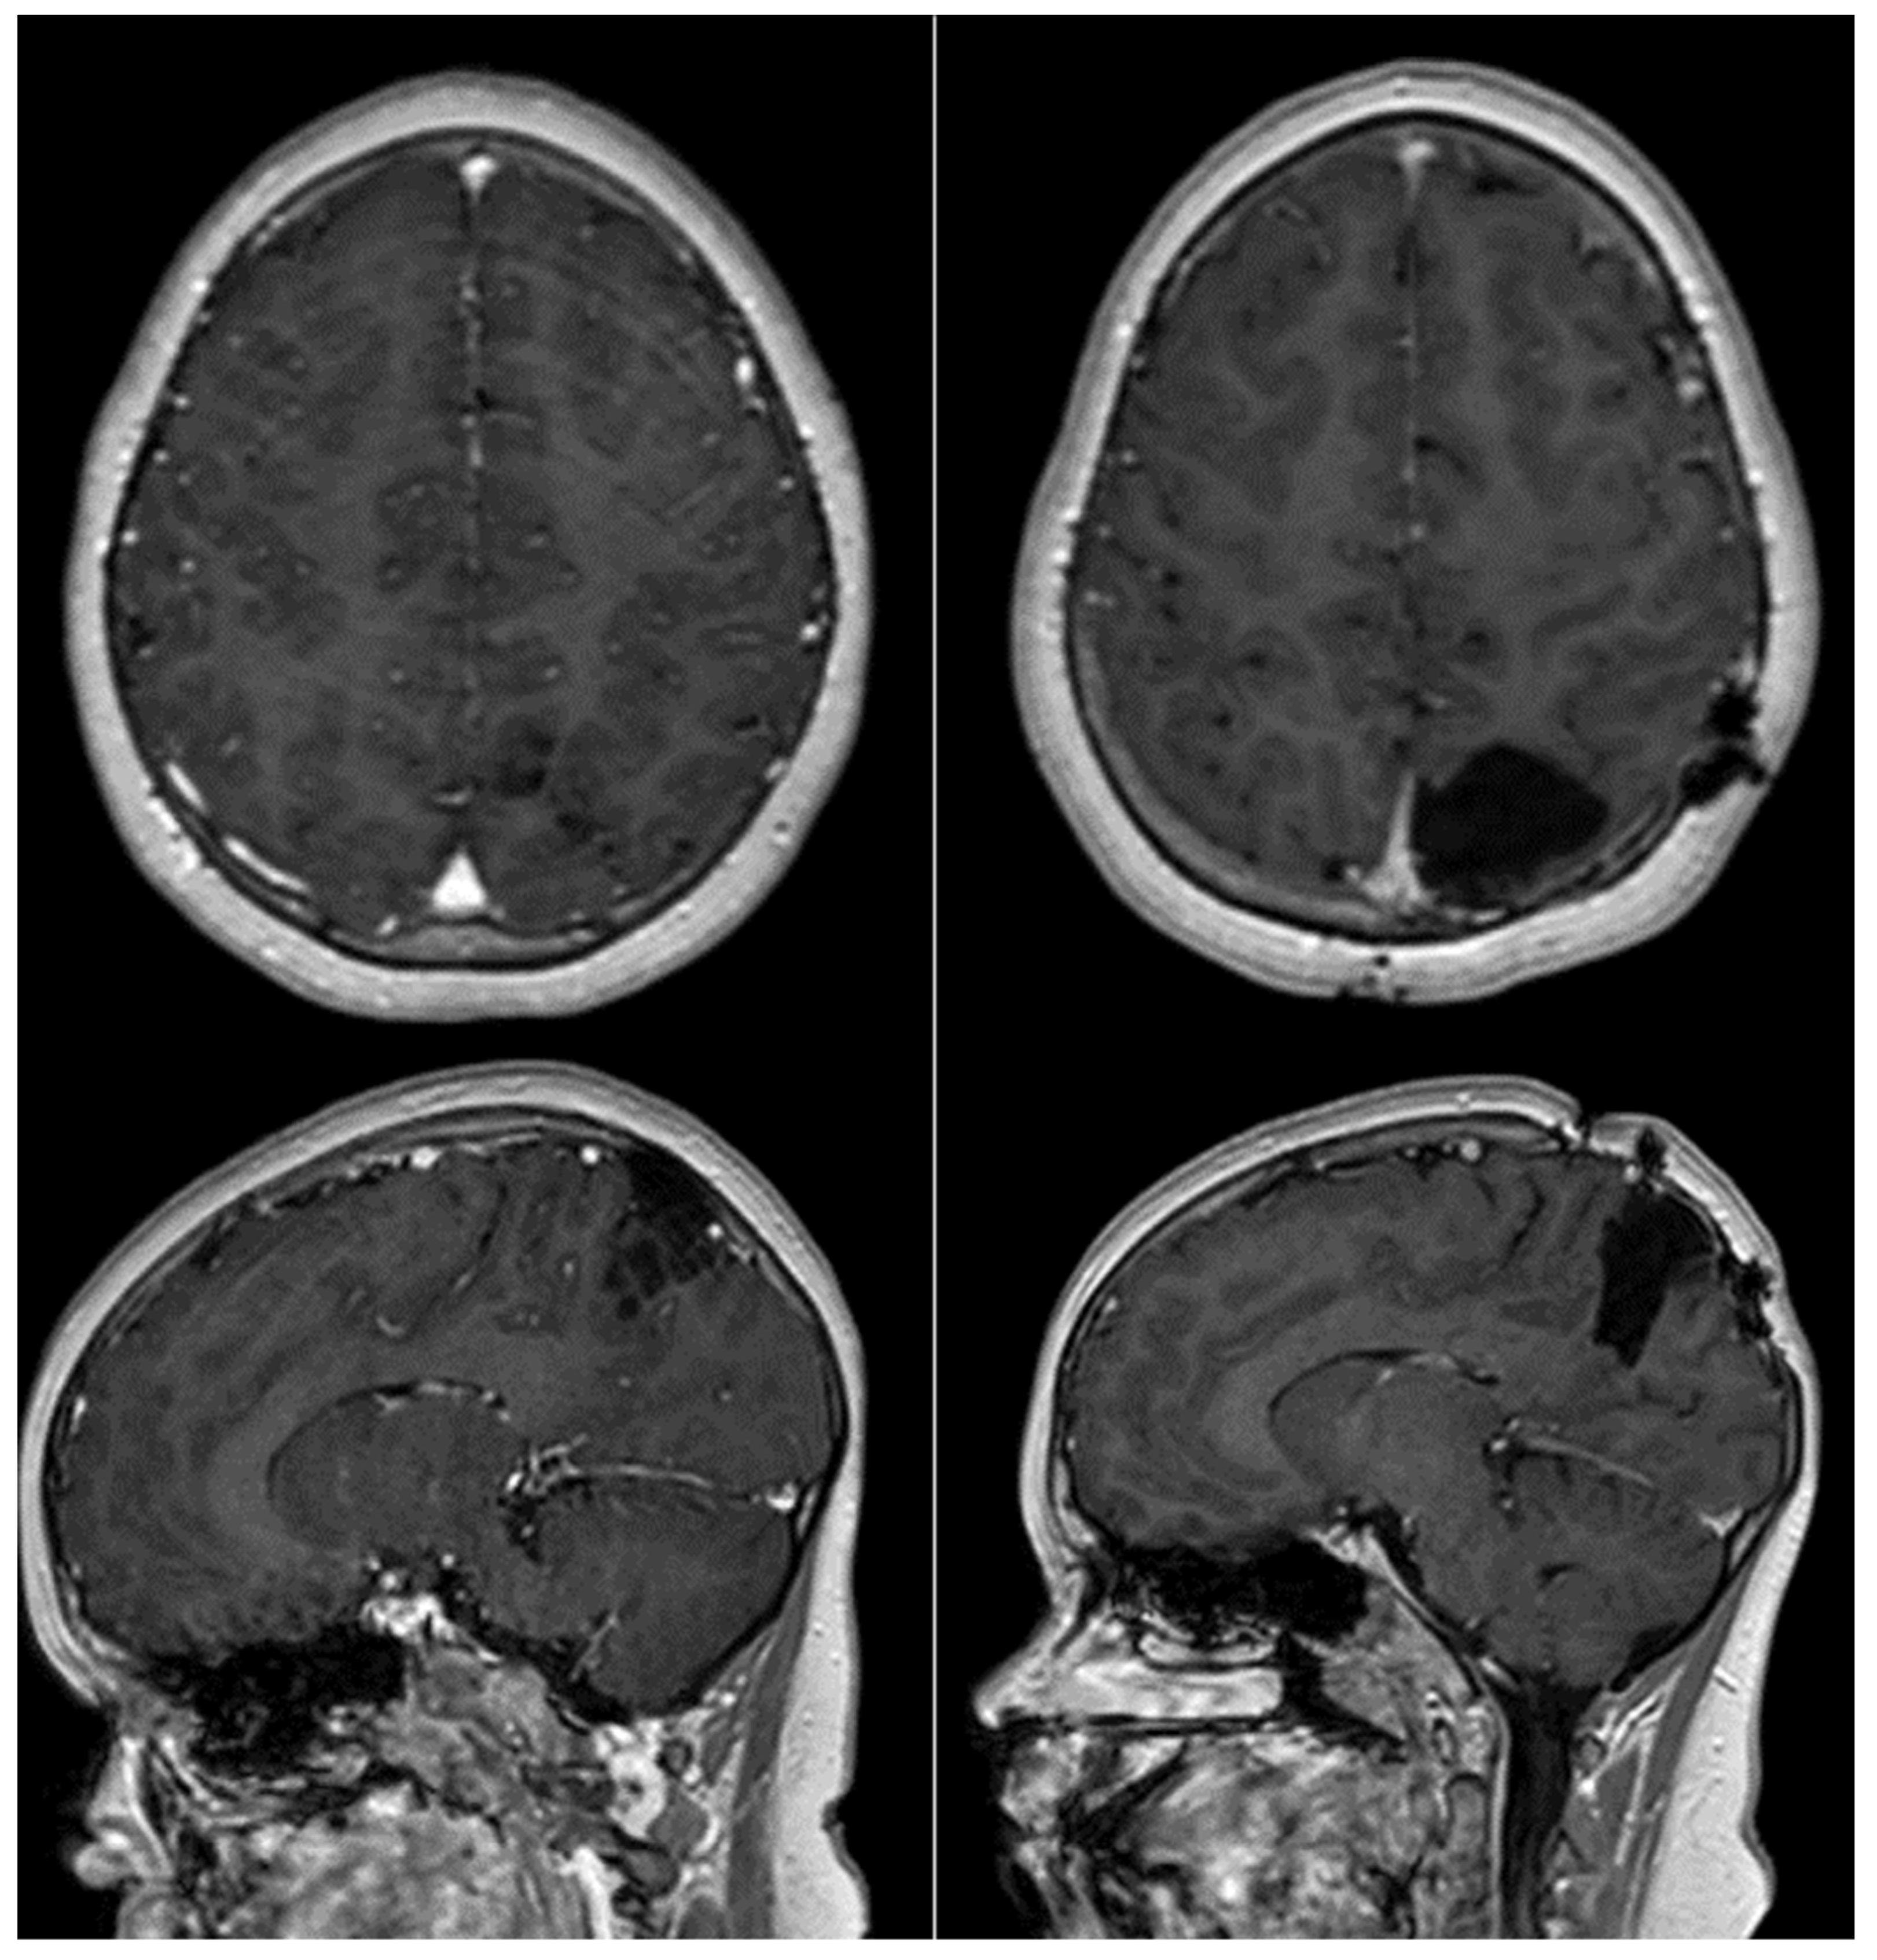

| Our case | 2023 | 8 | M | parietal | L | YES | GTR | NO |